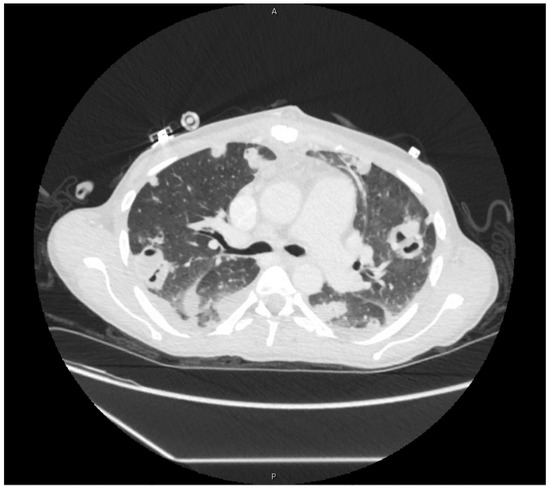

Postoperatively, she required vasopressor support and remained intubated. Her leukocytosis (19,000/μL) peaked on hospital day four, so IV piperacillin-tazobactam was restarted. Blood cultures taken the same day returned positive for MRSA. By hospital day six, she was extubated and weaned from vasopressor support. Antimicrobial therapy was again narrowed to IV vancomycin. Blood cultures taken on hospital day seven returned negative, and a treatment plan to receive six-weeks of IV vancomycin starting from this date was made. Imaging studies in the following days demonstrated cavitary lesions in both lungs (Figure 2) and possible C4–C5 vertebral discitis and osteomyelitis; however, no further surgical interventions were required. She was discharged on hospital day 18.

Figure 2. Cavitary lesions on computed-tomography scan of chest.